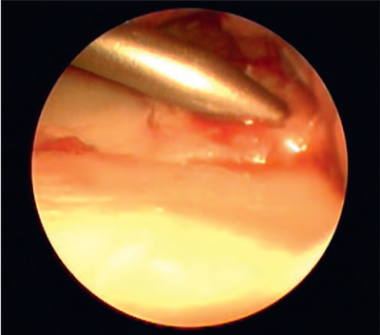

41 gadu vecam pacientam ar augstas enerģijas traumu pirms ārstēšanas uzsākšanas veikta rentgenogramma (sk. 5. A, B att.). Traumas dienā veikta lūzuma fiksācija ar ĀFA (sk. 6. att.), pēc piecām dienām – lūzuma osteosintēze ar volāro kompresijas plāksni un stieplēm plaukstas artroskopijas kontrolē (sk. 7., 8. att.). Pēcoperācijas rentgenogrammā redzama locītavas virsmu kongruences restaurācija abās standarta projekcijās (sk. 9. A, B att.).

7. attēls. Locītavas virsmas defekts un “trepe”, kuru vizualizē artroskopijas laikā / Articular step-off visualised during the arthroscopic surgery | 8. attēls. Defekta likvidēšana / Disposal of the defect |